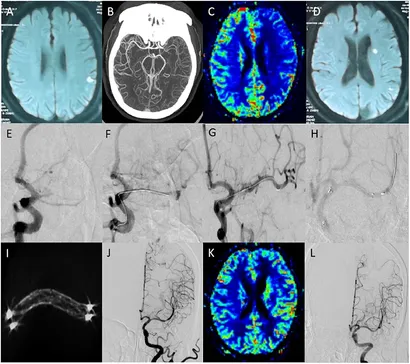

ENCYCLOPAEDIA of OCCLUSION【裁断済】。Spatial neglect after subcortical stroke may reflect cortico。fneur-13-1036661-g001.jpg。こちらの商品は裁断済商品になります。。【タイトル】本書は「ENCYCLOPAEDIA of OCCLUSION」として知られ、咬合に関する包括的な情報を提供します。図解!矯正治療が面白いほどわかる本 : 基礎知識-セファロ分析-診断-治療の実…。- タイトル: ENCYCLOPAEDIA of OCCLUSION- 出版社: The SHORIN Ltd.- 言語: 日本語- 状態: 経年劣化ありご覧いただきありがとうございます。ABGCEPD for acute symptomatic isolated cervical internal。購入後ScanすればiPadなどでいつでもどこでも読む事ができます。また再度メルカリに出品することができます。【新品】The Grasping Hand : 日本語版 : 手上肢の構造と機能。ガンステッドカイロプラクティック 科学&芸術。【出版社】この本はThe SHORIN Ltd.から出版されており、信頼性の高い資料です。【内容】咬合に関する詳細な知識を求める専門家や学生にとって、貴重なリソースとなるでしょう。犬と猫のロッキングプレート 裁断済み。健康・医学 year note 2026。

• Spatial neglect after subcortical stroke may reflect cortico

• fneur-13-1036661-g001.jpg

• ABGCEPD for acute symptomatic isolated cervical internal